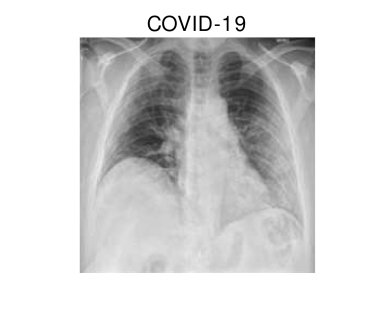

In hospitals, chest X-rays can mitigate these drawbacks by enabling a fast and reliable diagnosis. Figure 1 shows chest X-ray scans of healthy (top) and COVID-19 (bottom) patients in direct comparison. Even though patchy consolidations are recognizable in the COVID-19 scans, such X-rays remain challenging to interpret. Specialists, however, are able to identify the severity of a case early on and can take measures without waiting for lab results.